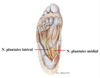

Identifiez